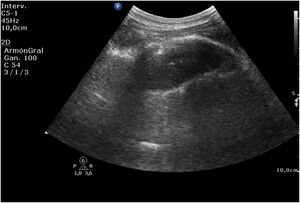

A las pocas horas, en el control sonográfico, se puede apreciar la endoprótesis (fig. 1) con sus pinzas (flechas en la figura 2) en la región del cuerpo gástrico, en la ventana esplenorrenal. A través de una endoscopia se recoloca la prótesis hasta su correcta ubicación. En seguimiento por ecografía, se comprueba la desaparición del dispositivo en el cuerpo del estómago (fig. 3).